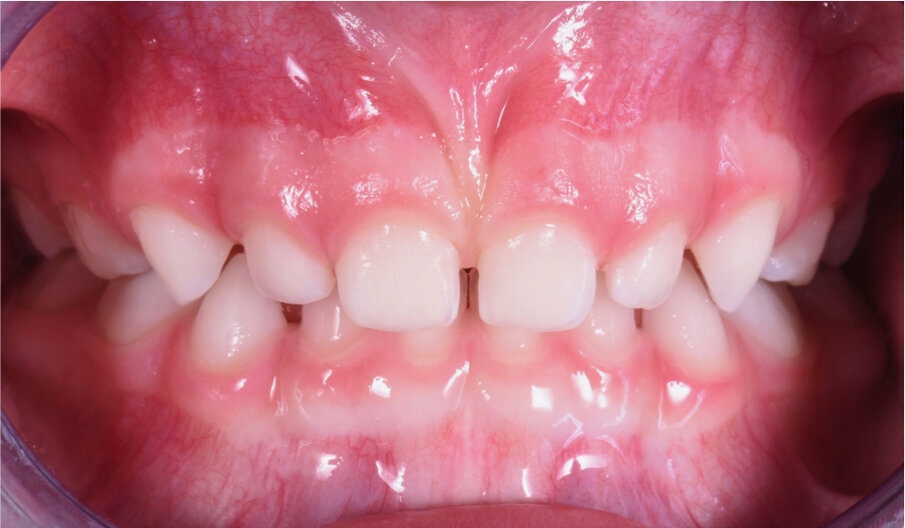

Caso 3 M.D.E Anni 2, succhiamento protratto del dito, deglutizione atipica, open bite dentale, contrazione arcata superiore. I genitori riferiscono difficoltà a respirare e raffreddori ricorrenti (Figg. 24-28).

Fig. 24

Fig. 25

Fig. 26

Fig. 27

Fig. 28

La paziente è stata trattata con un tipo particolare di AMCOP by Micerium a forma di “ciuccio”, il quale non richiede la presa dell’impronta, ideale per i pazienti in dentizione decidua e soprattutto per i pazienti di 2-3 anni con malocclusioni evidenti. I risultati sono stati ottenuti in 6 mesi di terapia, l’apparecchio è stato portato tutte le notti ed 1 ora durante il giorno. Dopo aver ottenuto il risultato l’AMCOP by Micerium viene portato per altri 6 mesi solo la notte per garantire la stabilità e per recuperare la funzione linguale e del muscolo orbicolare delle labbra.

Questo caso dimostra come la correzione della malocclusione funzionale, frequente nei bimbi a quest’età, sia il nostro primo obiettivo terapeutico.